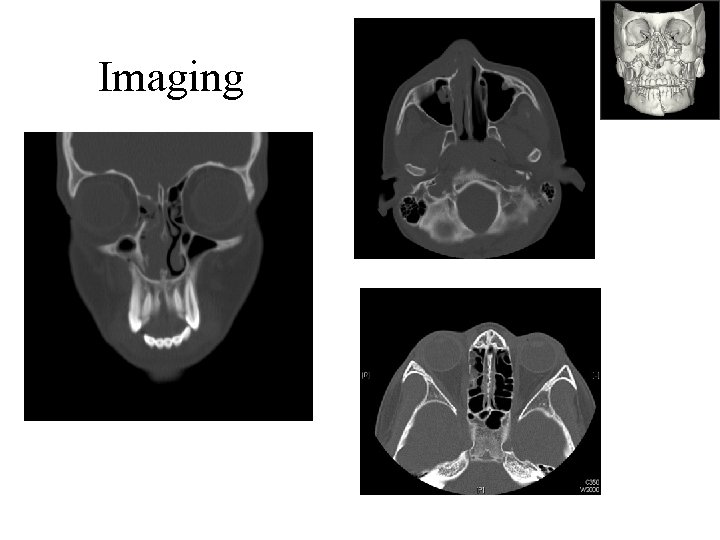

Imaging